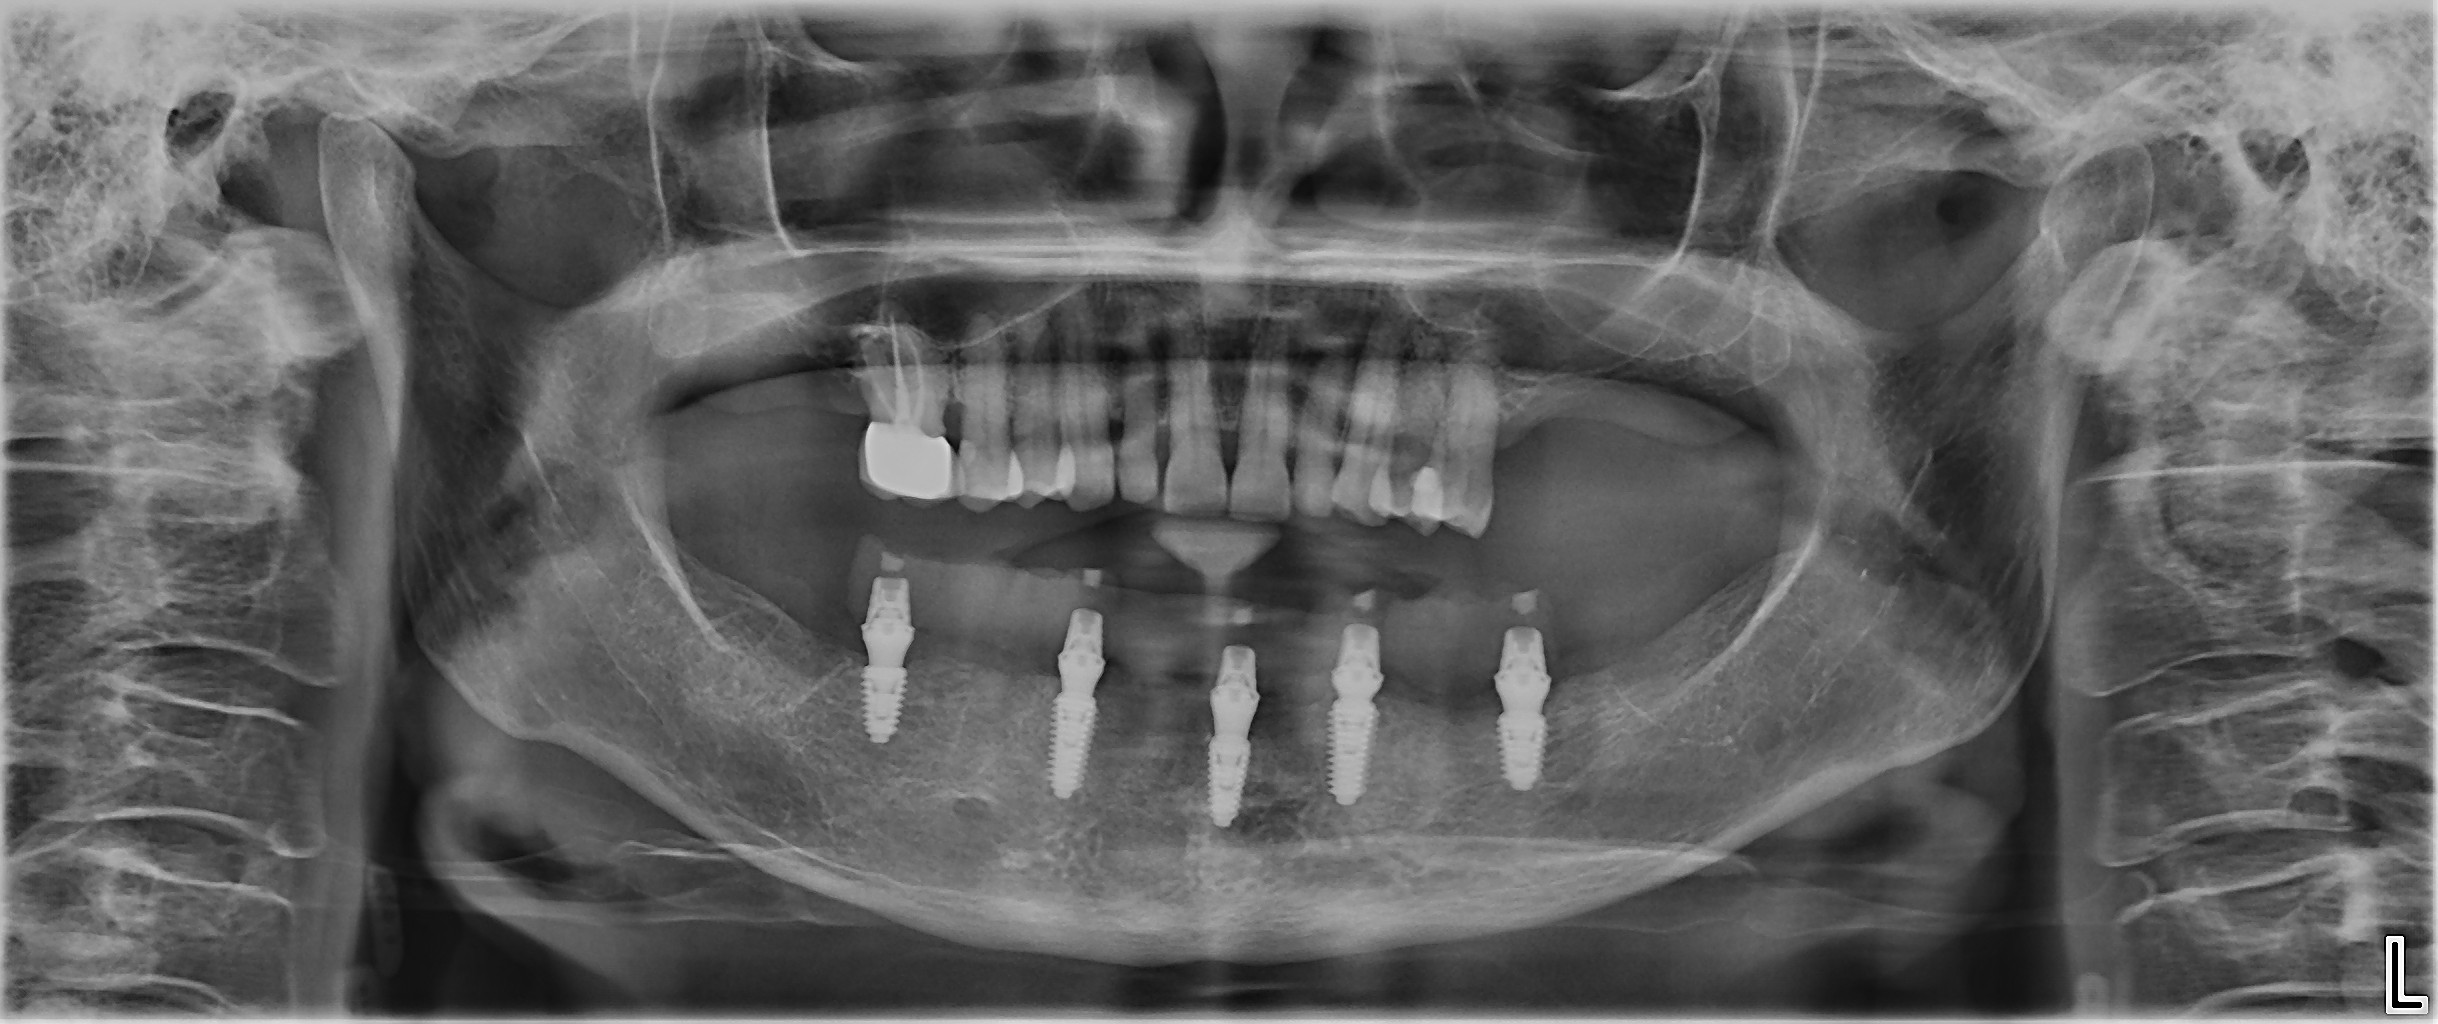

Fig. 16d: Final panoramic radiograph.

At the final delivery appointment, the definitive prosthesis was placed. A final radiograph was obtained to verify seating and fit, and then the prosthesis was torqued to 15 N cm as recommended. The occlusion and articulation were checked and adjusted as necessary. The screw access holes were sealed with PTFE tape and Shade A3 flowable composite (Figs. 16a-f). The patient was then instructed on hygiene and maintenance.